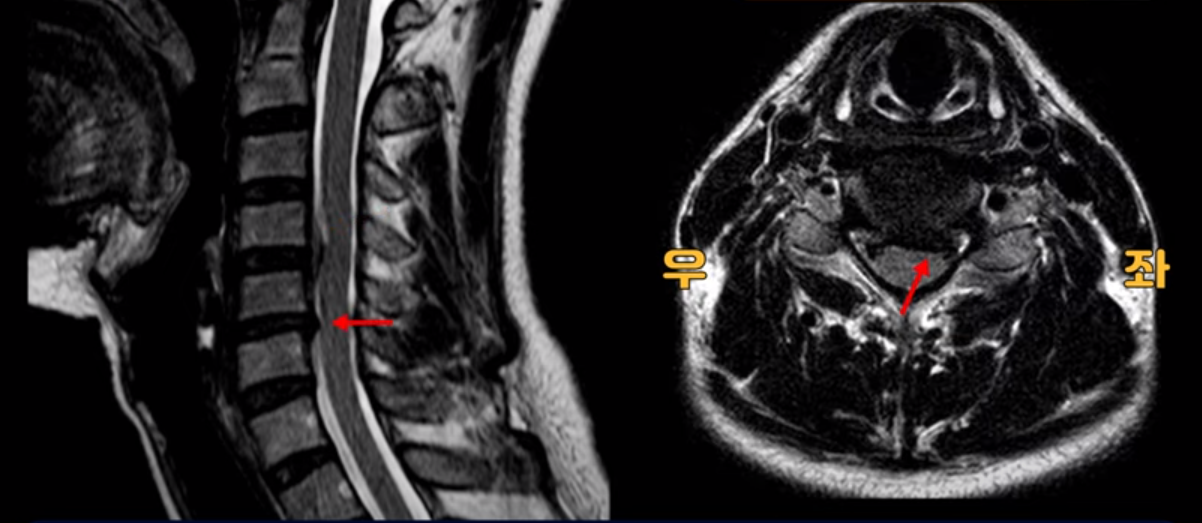

그래서 이게 오른쪽 통증의 원인일 수도 있고 아닐 수도 있습니다. 5번 6번은 왼쪽으로 밀려 나와있으니까 오른쪽 통증의 원인이 아닙니다.

그런데 이분 목을 보시면 여러 마디의 뼈가 퇴행이 진행되어 있습니다. 뼈가 깍두기처럼 각지고 예뻐야 하는데 끝이 조금씩 변형되어 뾰족하게 자라고 있습니다.

이런 게 협착을 일으킵니다. 그래서 우선 오른쪽 신경구멍 즉 추간공을 살펴보면 맨 위의 한마디를 빼고는 다 좁아져 있습니다.

특히 5번 6번 구멍이 가장 좁습니다. 이걸 협착이라고 합니다.

사실 여러 신경 구멍이 다 좁아져 있기 때문에 정확히 어느 마디가 방사통을 일으키는지 정확히 알기 어렵습니다. 그래서 만일 수술을 한다면 정확히 어느 마디가 진짜 원인인지 파악하지 못한 채 한다면 수술이 크게 실패할 수도 있습니다. 또한 이분처럼 여러 마디가 안 좋아서 수술한 마디의 위나 아래가 상태가 좋지 않으면 유합술 후 그 위나 아래에서 또다시 문제가 생기는 인접 분절 질환이 수술 후에 발생할 수도 있습니다. 이런 정도는 알아두는 게 좋습니다.